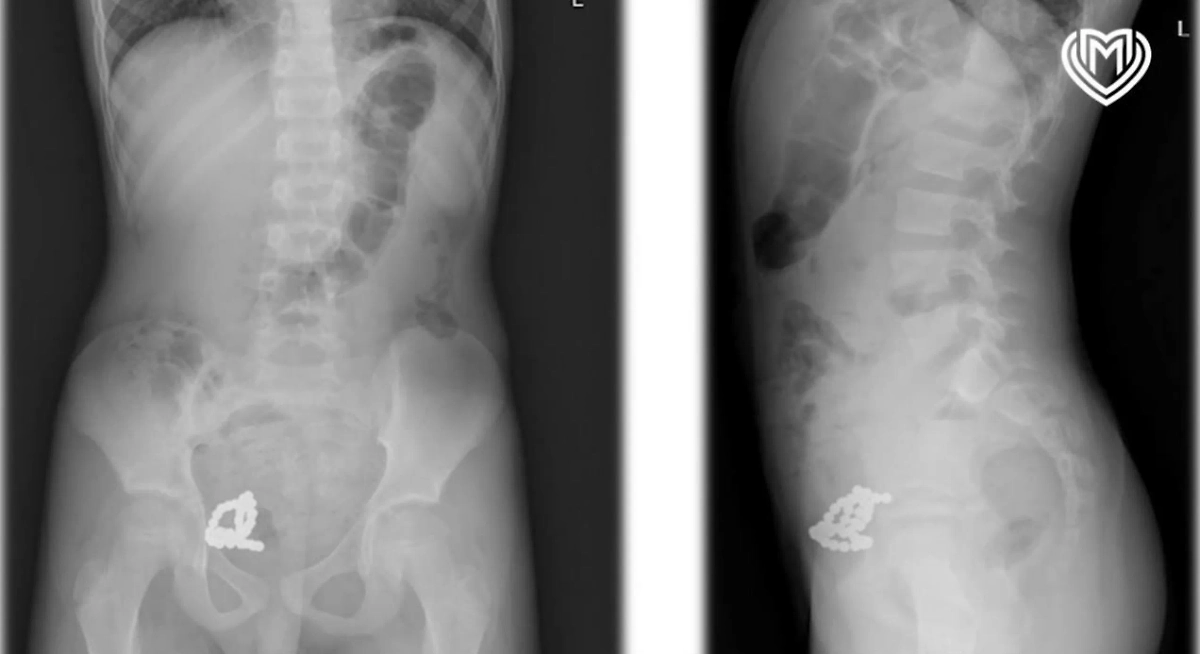

Рентген показал в организме мальчика целую коллекцию магнитиков. Фото © Предоставлено Life.ru

Обследование подтвердило наличие опасного скопления металлических предметов, что потребовало экстренного хирургического вмешательства.